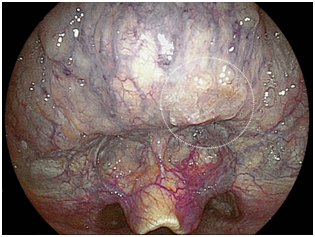

A 73-year-old male who had undergone esophagectomy for esophageal cancer 3months previously was admitted to our hospital with primary hypopharyngeal cancer. Before treatment, upper gastrointestinal screening was performed by trans-nasal endoscopy (model EG-L580NW, Fuji film, Co.). Using the intra-oropharyngeal U-turn method, an elevated lesion located at base of the tongue was easily detected in LCI mode (Figure 5A). We were able to obtain a clear image of the tumor without magnification at a close view.

Figure 5A LCI mode at a distance.

Superficial squamous cell carcinoma detected by trans-nasal endoscopy using intra-oropharyngeal U-turn method.

In BLI mode, irregular vessels around the tumor were clearly observed (Figure 5B). We were able to obtain a biopsy specimen without sedation, and confirmed the lesion to be squamous cell carcinoma. This patient had two other primary hypopharyngeal cancers, so he was treated by chemo-radiotherapy. This screening method is useful for a precise inspection before treatments in patients already known to have lesions.

Figure 5B BLI mode close-up.